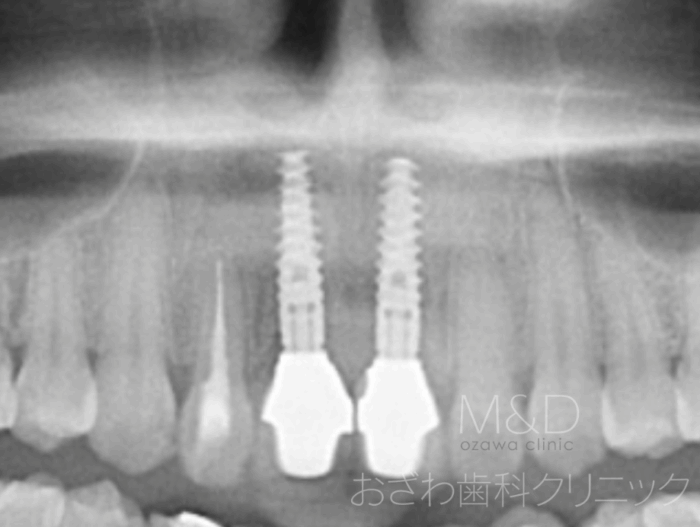

術後

インプラント2本即時負荷

(手術の日に仮歯が入ります)